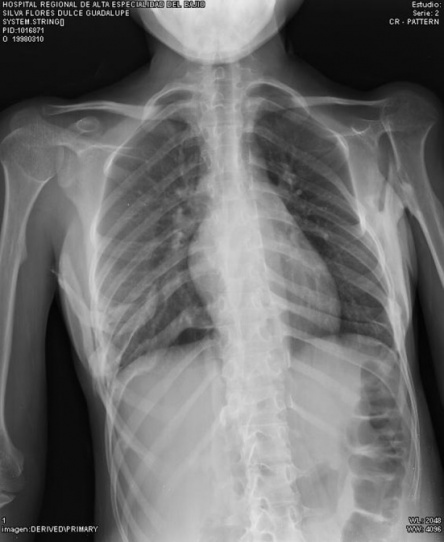

- Окостенение межреберных мышц[3]

- Дыхательные проблемы, вызванные грудной недостаточностью (например, уменьшенная подвижность грудной клетки)[5]

- Синдром грудной недостаточности, возможное жизнеугрожающее осложнение, которое может вызывать правостороннюю сердечную недостаточность и пневмонию. Максимизация функции легких и минимизация респираторных осложнений могут быть полезными для этих людей.[3]

- Рестриктивные заболевания легких (например, пневмония)[5]